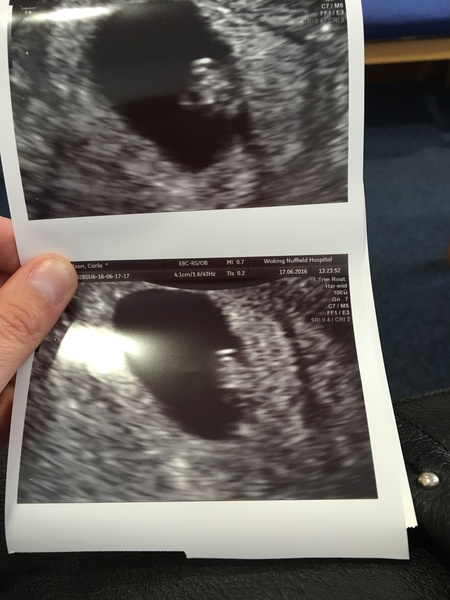

Hooray! Scan was good news, heartbeat of 130 and measuring 1cm, phew, can relax and enjoy the weekend a bit more now. Was dated for 2nd Feb.

I highly recommend having one if you can justify the extra cost... I went with babybond and the nurse was really lovely and professional

Our scan also went well. Saw the cutest little heart beat 😊 And measuring at 7.4mm :) back for another scan at 9+4 on 8th July x

A third 'yay' on the scan! Hb of 162 and measuring 8+2. I cried. So fucking relieved!